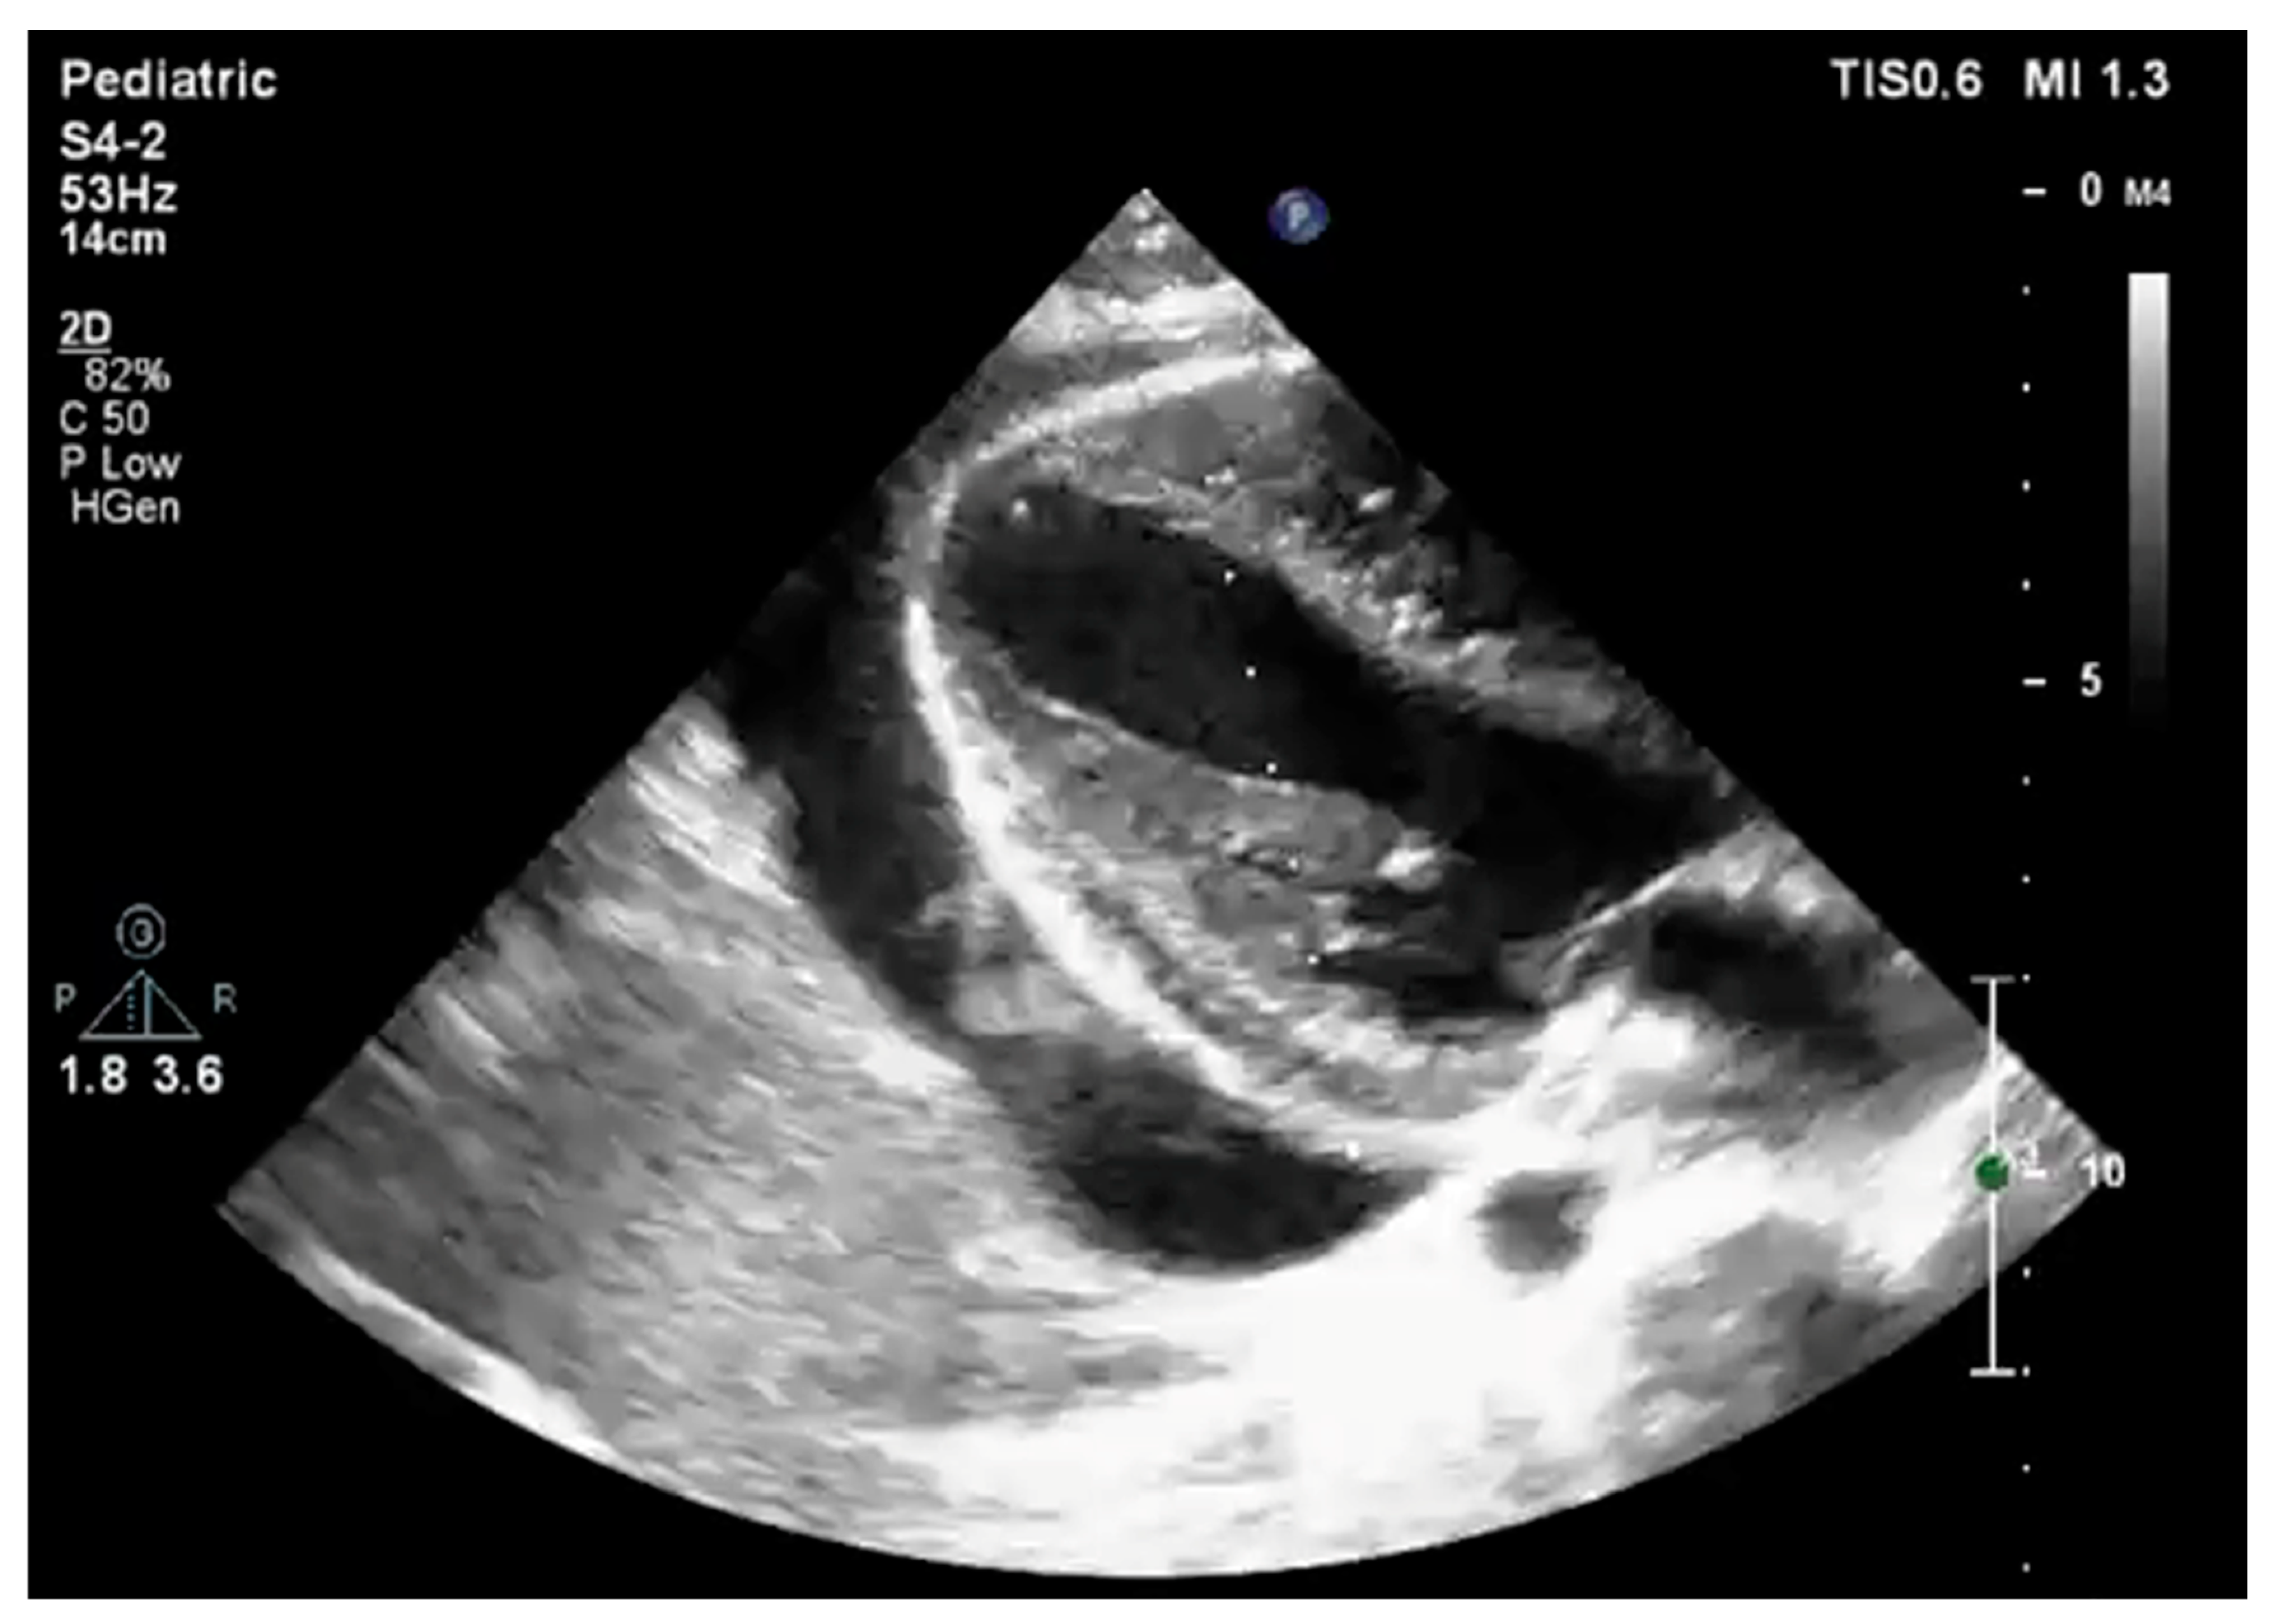

2. Case Report